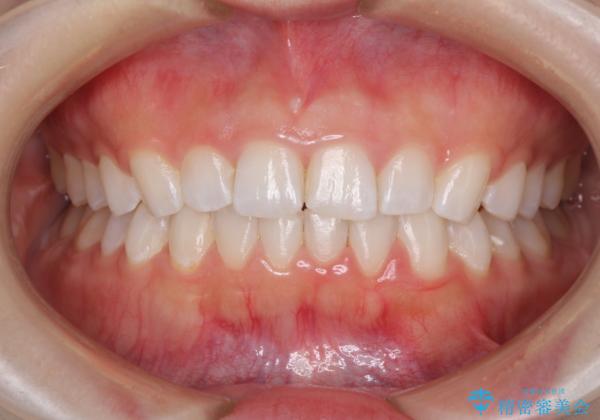

インビザラインは、装着していない時間がどれだけ短いかが、治療期間を大きく左右します。こちらの患者様は1日22時間以上、毎日欠かさず装着してくださったため、1年強という短期間で満足のいく歯列に整えることができました。